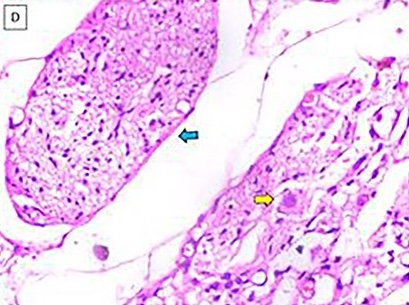

وبعد سلسلة من الفحوصات، شخّص الأطباء الحالة على أنها النسيج العصبي الدبقي المنتبذ، وهي حالة خلقية نادرة وغير خبيثة، تنمو فيها أنسجة دماغية ناضجة خارج الدماغ والحبل الشوكي. وعادة ما تُرصد هذه الحالة في منطقة الرأس أو العنق، إلا أن هذه الحالة كانت استثنائية، إذ وُجد النسيج العصبي عميقًا داخل البطن في منطقة خلف الصفاق.

وتُعد هذه الحالة شديدة الندرة، إذ لم يُسجَّل سوى ست حالات مشابهة فقط في الأدبيات الطبية الإنجليزية حتى الآن.